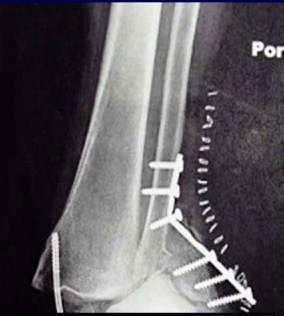

We don’t necessarily operate on all ankle fractures. The following x-ray demonstrates a stable ankle fracture (Figure 1).

This patient can start immediate, protected, weight bearing in a boot or air cast. If you’re not practicing that, you should! I still see elderly patients with a small “crack” like this, that are kept non-weight bearing for two months. Don’t do that! These are stable injuries. They can start immediate, protected, weight bearing in a boot, and can wean out of the boot as tolerated.